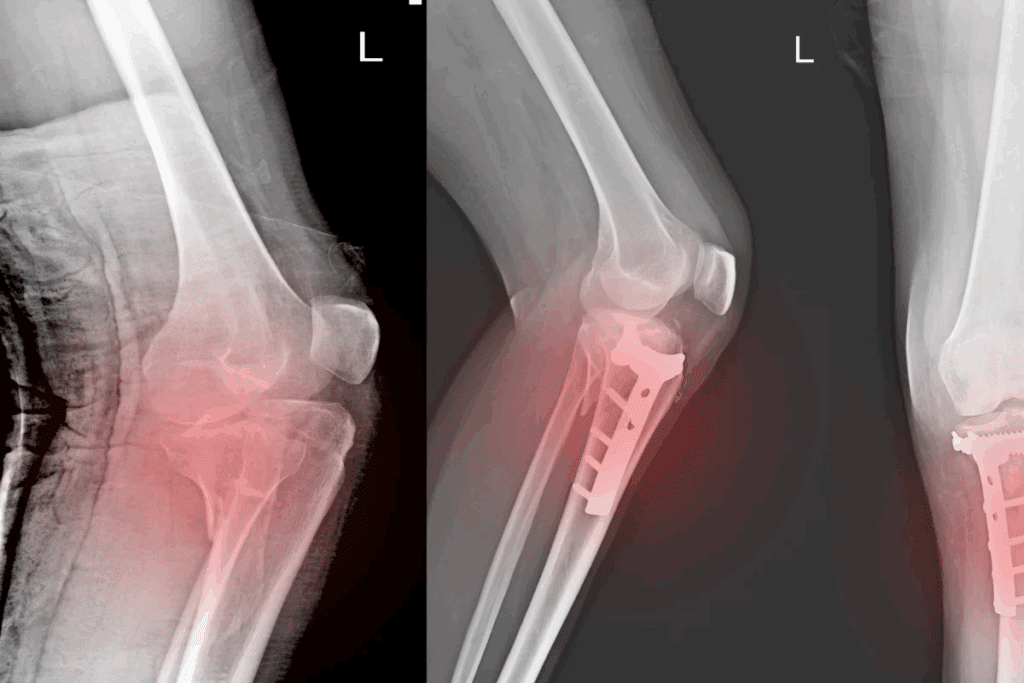

Imaging Techniques: X-rays, CT Scans, and MRIs

Imaging is key to confirming bone fractures. The right imaging depends on the fracture type, location, and patient’s health.

Common imaging techniques used include:

- X-rays: The first-line imaging modality for most suspected fractures, providing a quick and effective way to visualize bone structures.

- CT scans: Useful for complex fractures or when more detailed imaging is required, specially in cases involving multiple fragments or overlapping bones.

- MRIs: Particular value for detecting soft tissue injuries and stress fractures that may not be visible on X-rays.

Surgical Interventions: Pins, Plates, and Screws

For more serious fractures, surgery is needed. It ensures the bone heals right. Doctors use pins, plates, and screws to hold the bone together. This method is called internal fixation.